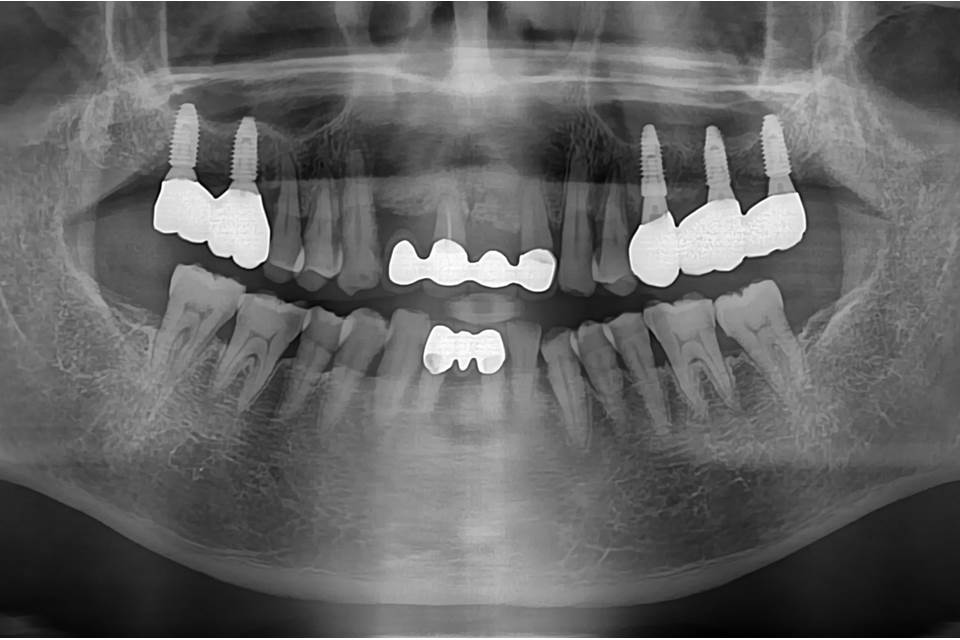

3-year follow-up panorama.

5-year follow-up panorama.

6-year follow-up panorama.